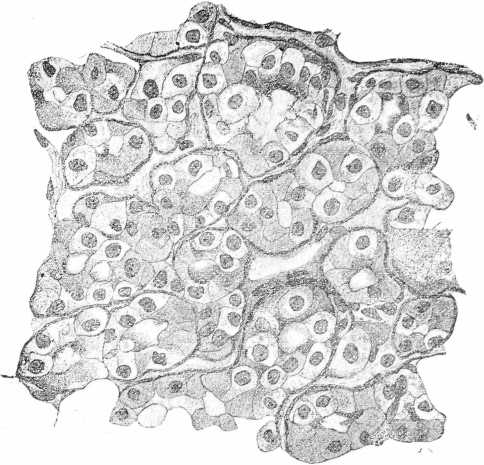

Наибольшія измѣненія въ щитовидной железѣ наступали подъ вліяніемъ тиреолитической сыворотки и адреналина, при чемъ подъ вліяніемъ этихъ агентовъ они развивались не съ одинаковой быстротой и не съ одной и той же интенсивностью. Скорѣе всего измѣненія щитовидной железы обнаруживались въ опытахъ съ тиреолитической сывороткой. Въ одномъ рядѣ случаевъ ихъ можно было наблюдать уже спустя 1 часъ послѣ впрыскиванія въ v. jugubaris 30 куб. цен. сыворотки. Въ это время удавалось констатировать умѣренное расширеніе сосудовъ, появленіе значительнаго количества большихъ эпителіальныхъ клѣтокъ въ стѣвкахъ фолликуловъ съ свѣтлой протоплазмой. Еще болѣе рѣзкія измѣненія приходилось встрѣчать при изслѣдованіи железы черезъ 6—24 часа (см. табл. II. рис. 3) послѣ впрыскиванія тиреолитической сыворотки. Протоплазма железистыхъ клѣтокъ представляется крайне набухшей, разрыхленной и пронизанной вакуолями, нѣкоторыя клѣтки превращались прямо въ сѣтку, въ которой виднѣлись довольно хорошо сохранившіяся ядра. Количество коллоидныхъ клѣтокъ въ одномъ рядѣ случаевъ казалось увеличеннымъ въ числѣ, въ другомъ оставалось въ предѣлахъ нормы. Величина фолликуловъ и степень растяженія ихъ коллоидомъ непостоянно, также постоянно измѣненіе калибра кровеносныхъ сосудовъ, непредставляющихся то болѣе, то менѣе широкими. Дальнѣйшія измѣненія щитовидной железы, насколько позволяютъ судить наши препараты, сводятся къ постепенному возвращенію органа къ нормальному состоянію. Протоплазма славныхъ железистыхъ клѣтокъ принимаетъ вновь зернистый видъ. Вакуоли занимаютъ только небольшую частъ клѣтки. Этотъ процессъ возстановленія обычной структуры клѣточнаго тѣла происходитъ въ однихъ случаяхъ довольно быстро, такъ что по истеченіи уже 24 часовъ щитовидной железѣ наблюдается картина, почти соотвѣт ствующая уже той, которая встрѣчалась у нормальныхъ животныхъ. (См. табл. III. рис. 5). Въ другихъ случаяхъ тотъ же процессъ идетъ гораздо медленнѣе и по истеченіи 48 часовъ на препаратахъ изъ щитовидной железы можно было встрѣтить еще глубокія измѣненія строенія въ фолликулахъ съ преобладаніемъ сильно разбухшихъ, безцвѣтныхъ, лишенныхъ нормальной зернистости протоплазмы клѣтокъ, ядра которыхъ частью были смѣщены и окрашивались диффузно. (См. табл. II, рис. 4).

Рис. 3. Срѣзъ изъ щитовидной железы кошки спусти 24 часа послѣ впрыскиванія тиреолитической сыворотки. Фиксація въ 10% формалинѣ. Окраска гематоксилиномъ и эозиномъ. Увеличеніе: Leitz. Ocular 4, Object 6.

Рис. 5. Срѣзъ изъ щитовидной железы кошки спустя 24 часа послѣ впрыскиванія тиреолитической сыворотки. Фиксація въ 10% формалинѣ, окраска гематоксилиномъ и эозиномъ. Увеличеніе: Leitz, Ocular 5. Object. 7.